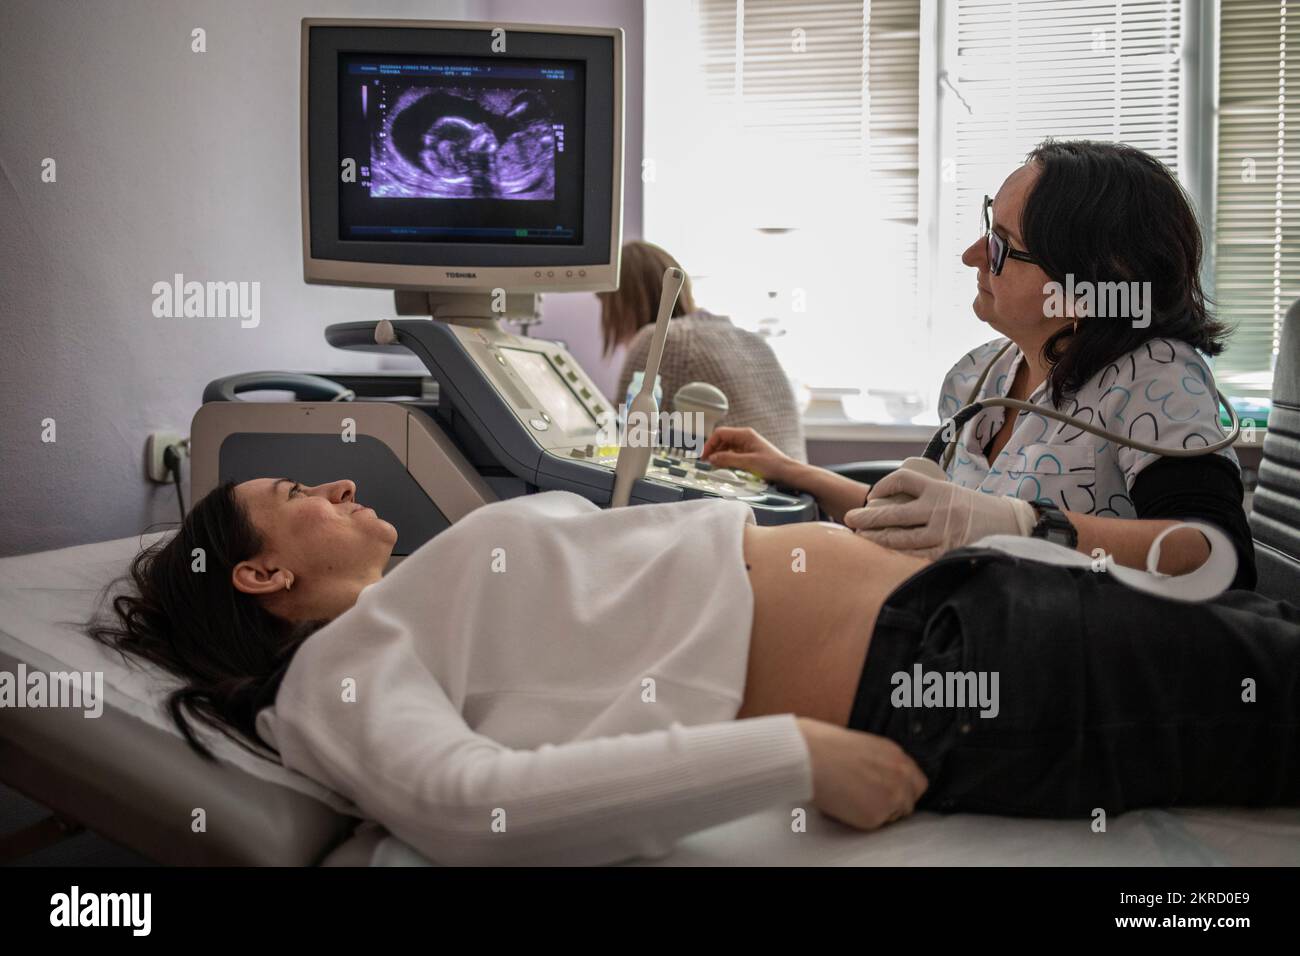

Victoria, 38, che è incinta di 16 settimane, fa una scansione del bambino presso l'ospedale maternità No.5 il 4 aprile 2022, nella città portuale meridionale di Odesa, Ucraina. Foto Stockhttps://www.alamy.it/image-license-details/?v=1https://www.alamy.it/victoria-38-che-e-incinta-di-16-settimane-fa-una-scansione-del-bambino-presso-l-ospedale-maternita-no-5-il-4-aprile-2022-nella-citta-portuale-meridionale-di-odesa-ucraina-image496313169.html

Victoria, 38, che è incinta di 16 settimane, fa una scansione del bambino presso l'ospedale maternità No.5 il 4 aprile 2022, nella città portuale meridionale di Odesa, Ucraina. Foto Stockhttps://www.alamy.it/image-license-details/?v=1https://www.alamy.it/victoria-38-che-e-incinta-di-16-settimane-fa-una-scansione-del-bambino-presso-l-ospedale-maternita-no-5-il-4-aprile-2022-nella-citta-portuale-meridionale-di-odesa-ucraina-image496313169.htmlRF2KRD0E9–Victoria, 38, che è incinta di 16 settimane, fa una scansione del bambino presso l'ospedale maternità No.5 il 4 aprile 2022, nella città portuale meridionale di Odesa, Ucraina.